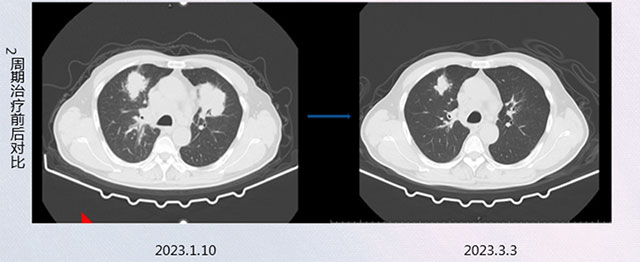

3月初,两周期的治疗结束后,卢大爷再次复查CT与核磁共振,与之前两次检查结果比较,情况明显好转。

据李静介绍,一般肺癌病人的化疗方案通常采取单纯化疗、化疗+免疫或化疗+抗血管的方案,而卢大爷的全身情况较好,能够耐受多药联合导致的副反应,可使疗效最大化,因此采用了四药联合化疗方案。事实证明:此方案对于卢大爷缩瘤效果明显,同时没有明显的不良反应,卢大爷的耐受性及可及性均较好。